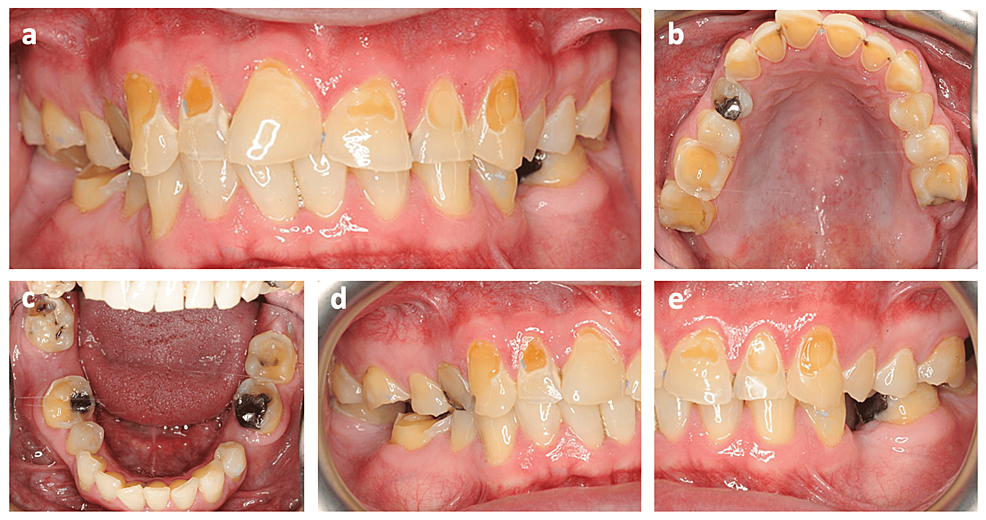

Tooth Surface Loss Bdj . There is marked tooth surface loss affecting the anterior teeth, particularly the central incisors where the pulps are visible. Generalised wear is more difficult; Tooth surface loss (tsl) can be defined as ‘surface loss of dental hard tissues by causes other than caries, trauma or developmental defects: Treatment options and guidance for managing patients who present with tooth surface loss. Tooth surface loss may be purely physiological (fig 1) and occurs as a natural consequence of ageing. The management of this form of. Space is created by increasing the occlusal vertical dimension. This chapter aims to consider ways of. This part of the series is devoted to tooth surface loss (tsl) not caused by caries or trauma.